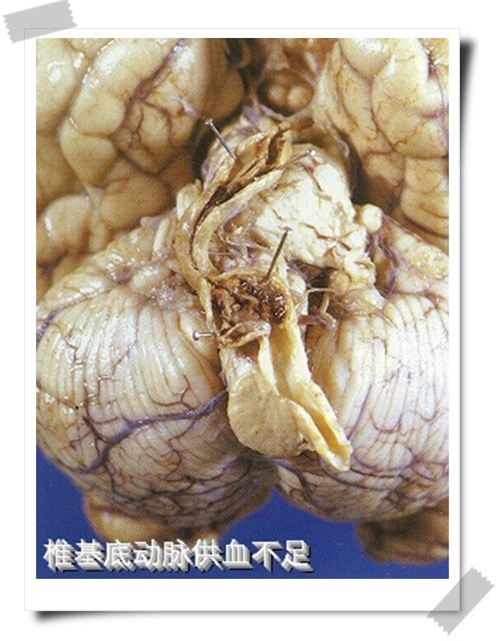

椎基底動脈供血不足腦梗塞

小腦腦梗塞組圖

小腦腦梗塞